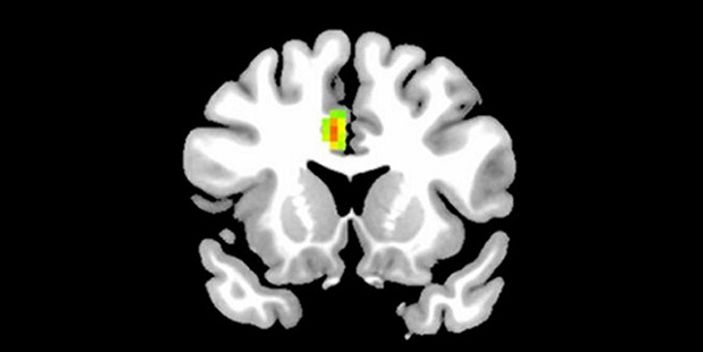

Aşık insanların beyin MR'ı çekildi(Aşık olmayan bir insanın beyni)

Araştırma sonucuna göre, aşıkken beynimize giden kan miktarı artıyor ve beynimizin 12 bölgesi aktif oluyor. Beynin önde gelen fonksiyonel değişiklikleriyle ilgili ilk amfirik kanıtını gözler önüne seren araştırma, aşkın insanlar üzerindeki etkilerini tam olarak açıklığa kavuşturmasa da işe bir yerlerden başlıyor.